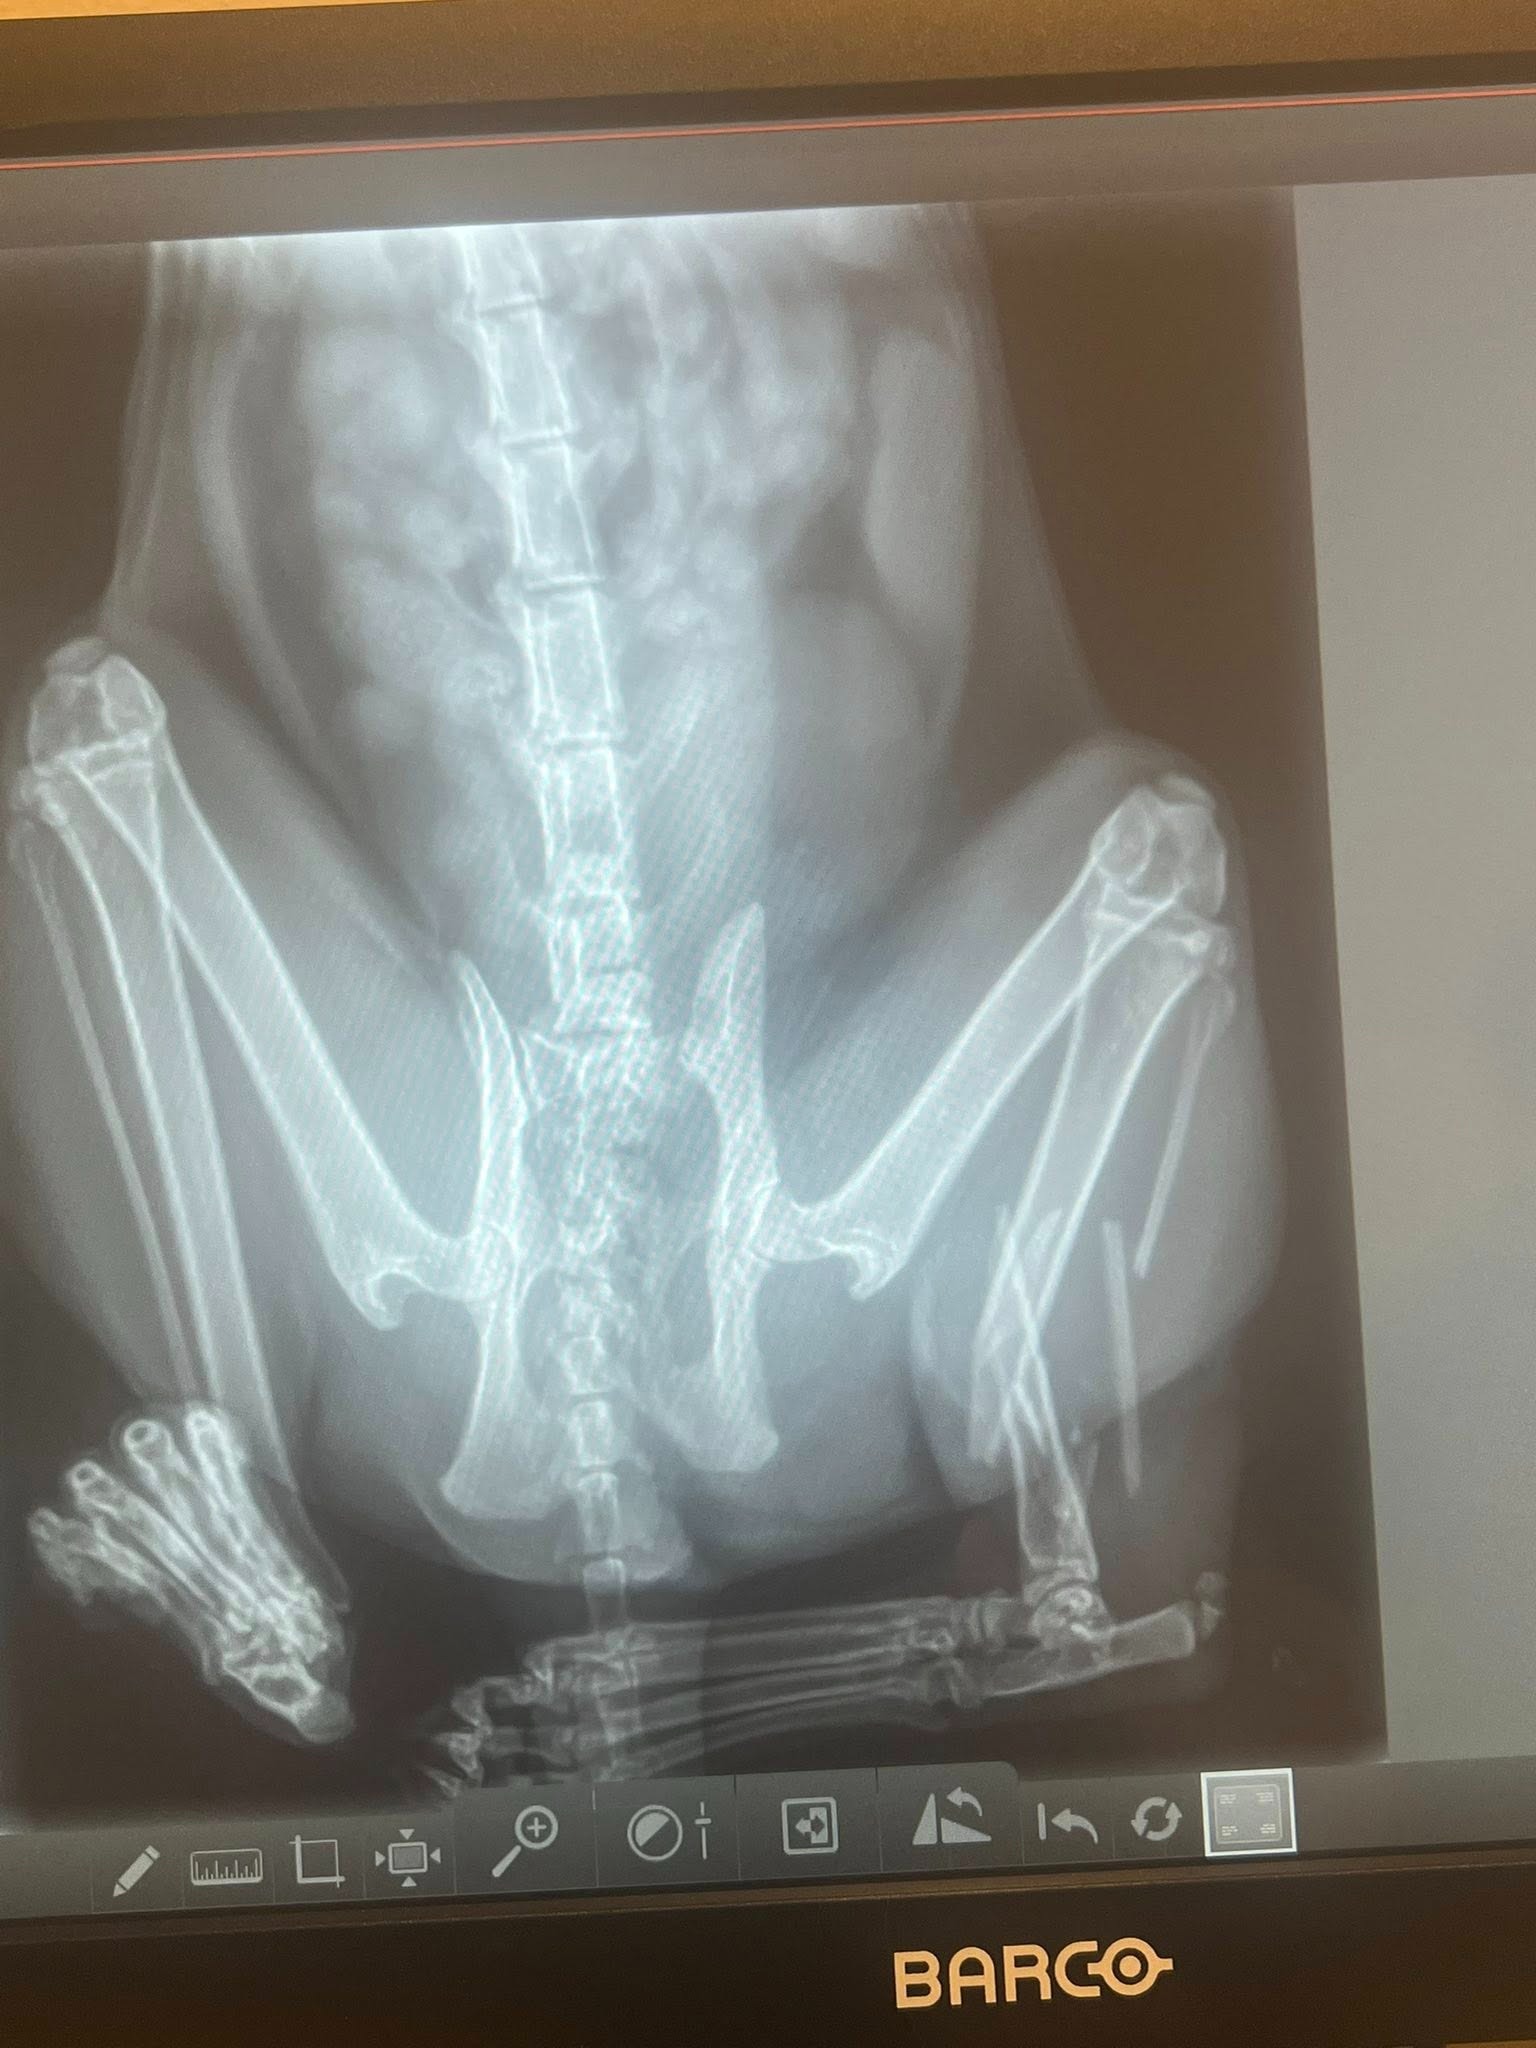

On the morning of May 8, 2025, my sister Maiya's cat Skippy was found severely injured after being struck by a car. Left alone overnight, he was discovered the next day and rushed to emergency care. Skippy is currently hospitalized with a broken hip and leg, and his nerves are severely damaged, affecting his bladder and tail function. Due to the extent of his injuries, amputation of his leg may be necessary to prevent further complications.

Ongoing Treatment: Skippy is awaiting additional X-rays to assess the full extent of his injuries.

Possible Amputation: Due to nerve damage, amputation of his leg may be necessary to prevent further complications.